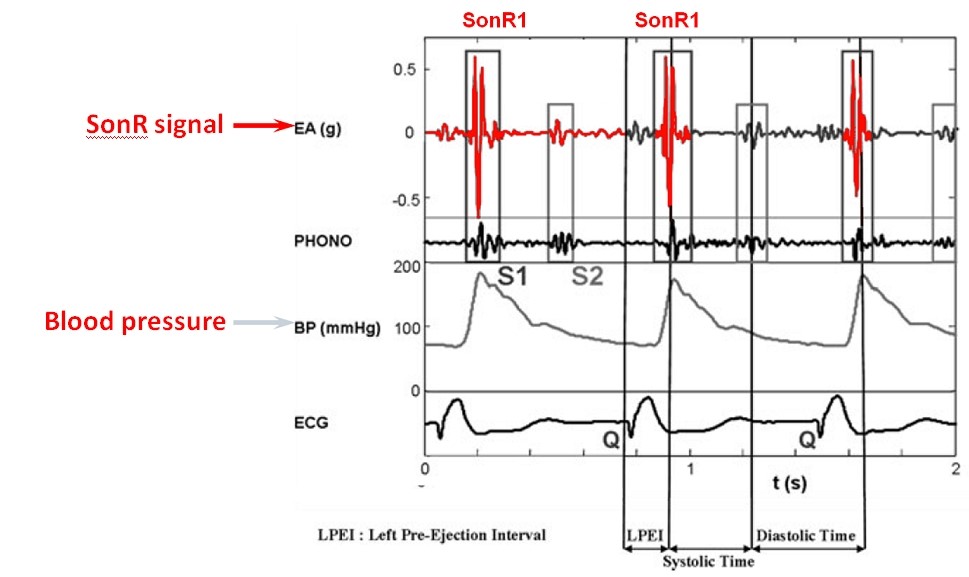

Le SonR® Le capteur hémodynamique micro-accéléromètre est enfermé dans une capsule scellée à l'extrémité d'une sonde de stimulation auriculaire (sonde SonRtip compatible IS-1).

Le capteur mesure en g (m/s2) les micro-accélérations du myocarde tout au long du cycle cardiaque ; le SonR1, l'un de ses principaux composants, est créé par la contraction iso-volumique.

La composante SonR1 de ce signal correspond au premier bruit cardiaque S1. Ses variations sont corrélées aux variations du VG maxdP/dt.